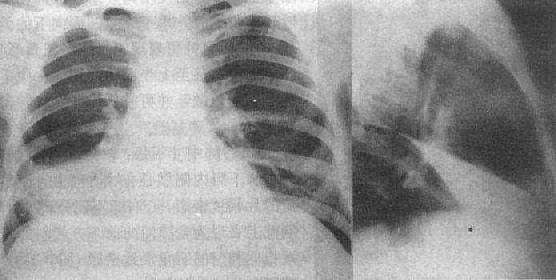

1、全肺不张

患侧密度均匀升高,即患侧比健侧发白,而且患侧肋骨之间空隙变窄,膈肌上移,胸廓塌陷,而位于两肺中间的心脏、气管均向患侧移位,甚至健侧的肺组织也越过中线、倾向患侧,形成肺疝。

右侧全肺不张

2、右肺叶不张

右肺有3叶,上叶肺不张可见右上部分出现三角形或带状高密度影。此常见于肺结核或中央型肺癌所致的肺不张。中叶肺不张可在心脏右侧旁边见到三角形致密影,其尖角指向外侧,纵隔、心脏等位置一般没有改变。下叶肺不张可见心脏旁边一个三角形致密影,尖角指向肺门,而且心脏、纵隔均向患侧移动。

右肺中叶肺不张

3、左肺叶不张

左肺有2叶。左肺上叶肺不张可见左肺门处一团阴影,纵隔边界模糊不清,出现典型的空气新月征和Luftsichel征。左肺下叶肺不张可见心脏后面出现三角形致密影。此外还有圆形肺不张,线状肺不张等类型。